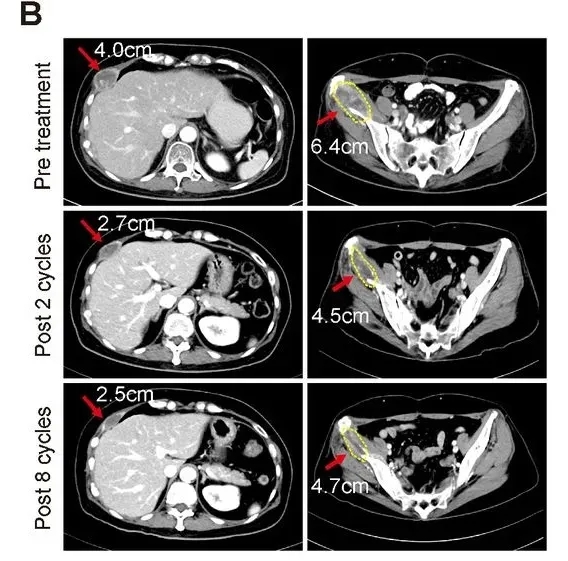

NK细胞联合曲妥珠单抗,让耐药晚期HER2阳性乳腺癌实现长期病情稳定

《临床癌症研究》曾报道一项“自体NK细胞联合曲妥珠单抗治疗HER2阳性乳腺癌”的Ⅰ期临床试验振奋数据。该研究共纳入19例18~75岁、对标准治疗耐药的HER2阳性晚期乳腺癌患者,均接受这一联合治疗方案。

结果显示:6例患者达到病情稳定(SD),缓解持续时间均≥6个月(范围6~12个月)。

值得关注的是,其中1例55岁转移性激素受体阳性+HER2阳性乳腺癌患者还实现了部分缓解(PR):该患者既往已接受抗HER2治疗、激素疗法及多种化疗,经连续2个周期联合治疗后达PR,且这一状态持续至第8周期(详见下图)。此外,该患者的肿瘤标志物CA-153水平显著下降,治疗前为146.8,治疗第5周期降至75.4,治疗结束时仍稳定在76.6。

▲图源“AACR”,版权归原作者所有,如无意中侵犯了知识产权,请联系我们删除